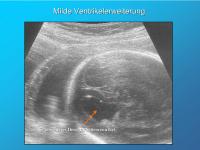

Milde Ventrikelerweiterung

Abbildung 4

Keywords:

Seitenventrikel

Ventrikelerweiterung